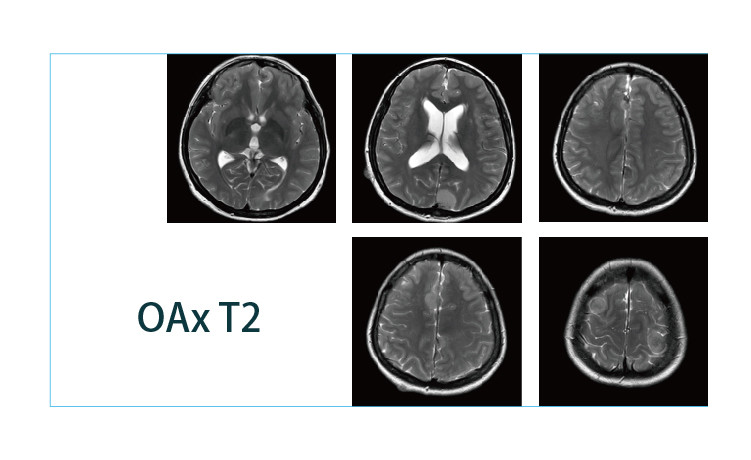

【朗润影像档案】20190412磁共振影像病例结果讨论